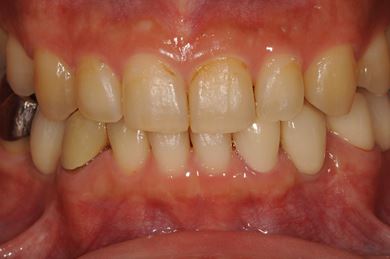

インプラントの症例写真 IMPLANT

骨再生インプラント治療

| 性別/年齢 | 男性 / 34歳 | ||||||||||||||||||||||||||||||||

| 治療方針 | ソケットリフトにて上顎洞を拳上し、インプラント治療を可能にする。 | ||||||||||||||||||||||||||||||||

| 治療内容 | インプラント1本(ソケットリフト)、メタルボンドセラミッククラウン1本 | ||||||||||||||||||||||||||||||||

| 総治療費 | 547,838円 | ||||||||||||||||||||||||||||||||

| 治療期間 | 4ヶ月 |